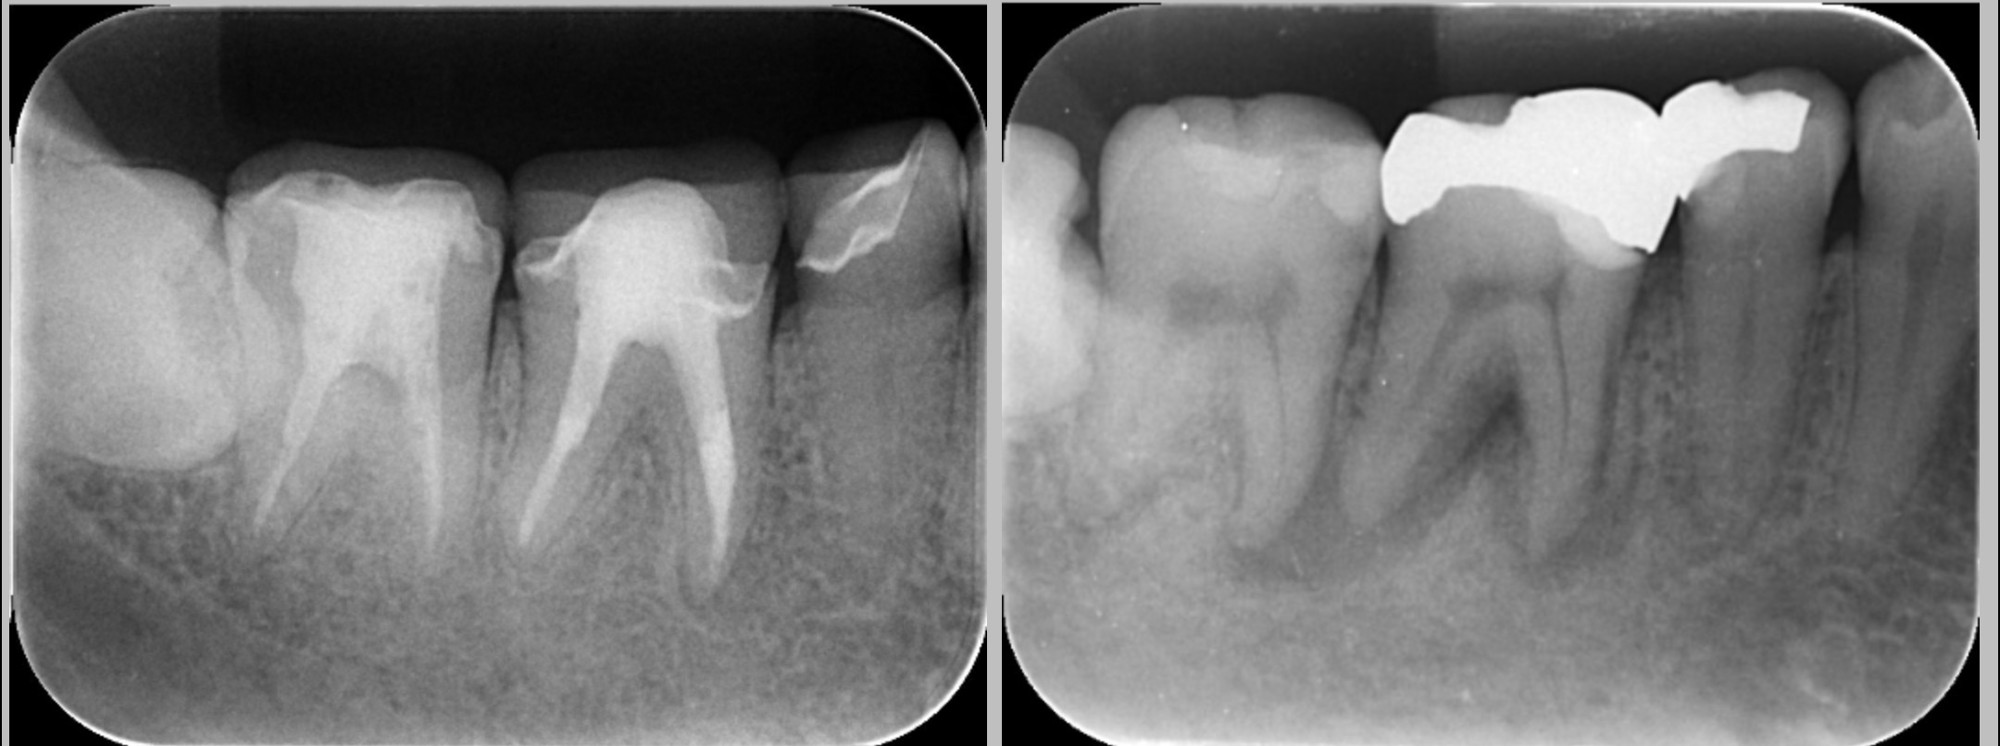

根管治療は“回数”より“設計”が重要

根管治療は、従来複数回の通院が必要とされることが多い。

しかし診断精度や設備、治療計画によっては、

症例に応じて比較的少ない通院回数で完結するケースもある。

重要なのは、

・感染状態の正確な評価

・マイクロスコープ下での精密処置

・治療後の被せ物までを含めた計画立案

である。

単に回数を減らすことではなく、

神経治療から補綴までを一連の流れとして設計することが、

渡航前治療では特に求められる。

さらに、根管治療が途中、もしくは治っていないで放置してしまった場合は、将来の抜歯のリスクが高くなってしまいますので注意が必要である。